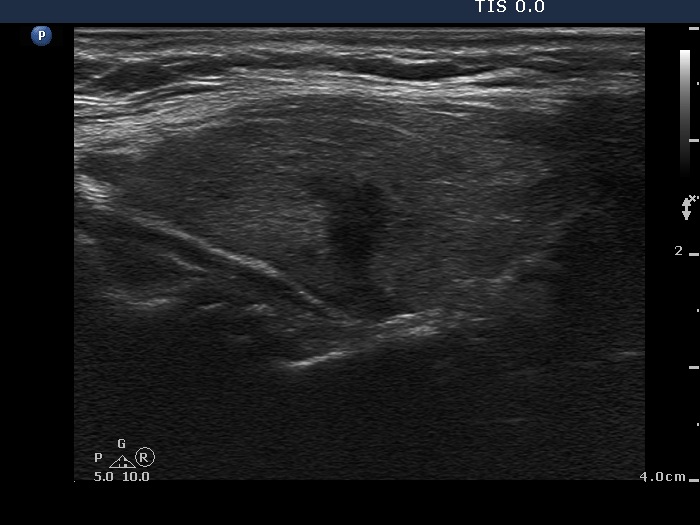

Follow-up investigation 6 months after first visit (third row of images):

Ultrasonography. Except for a minimal decrease in hypoechogenicity and in the vascularization the pattern was unchanged.